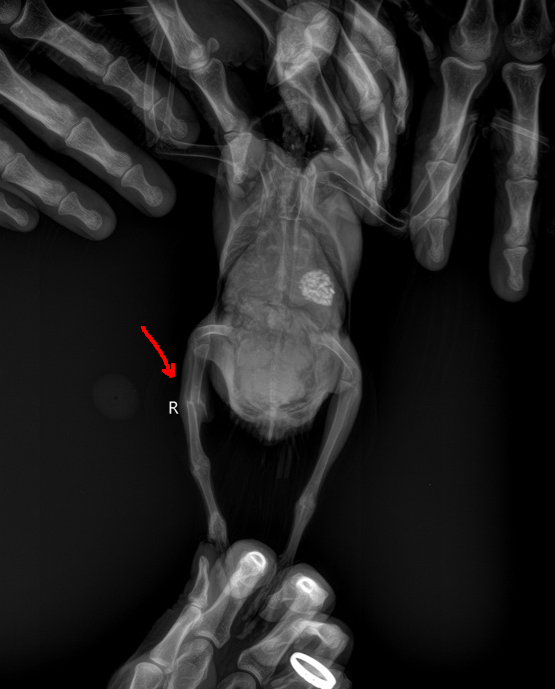

У птицы, к сожалению, перелом кости со смещением. Сложно сказать во сколько обойдется операция если снова ломать и ставить кости правильно под наркозом. Плюс с птицами по большей части клиники не работают. Из 10 ветклиник с рентгеном при прозвоне согласились сделать его птице только 2 (!!!). Причем в одной из тех что согласились, согласились на рентген только при условии, что плюсом к рентгену будет еще докуплен прием врача за 2500 рублей. И только в одной согласились сделать чисто рентген и все. Но они операциями не занимаются. Какие перспективы у птицы, если оставить все как есть?